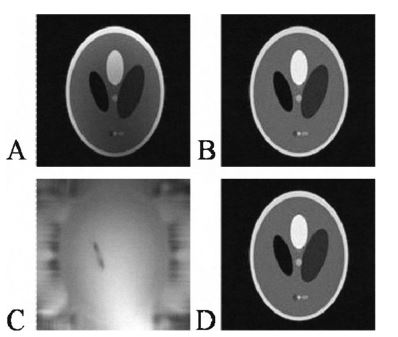

In this study, we propose a novel data acquisition and image reconstruction method for parallel magnetic resonance imaging (MRI). The proposed method improves the GRAPPA algorithm by simultaneously collecting data using the body coil in addition to localized surface coils. The body coil data is included in the GRAPPA reconstruction as an additional coil. The reconstructed body coil image shows greater uniformity over the field of view than the conventional sum-of-squares (SoS) reconstruction that is conventionally used with GRAPPA. The body coil image can also be used to correct for spatial